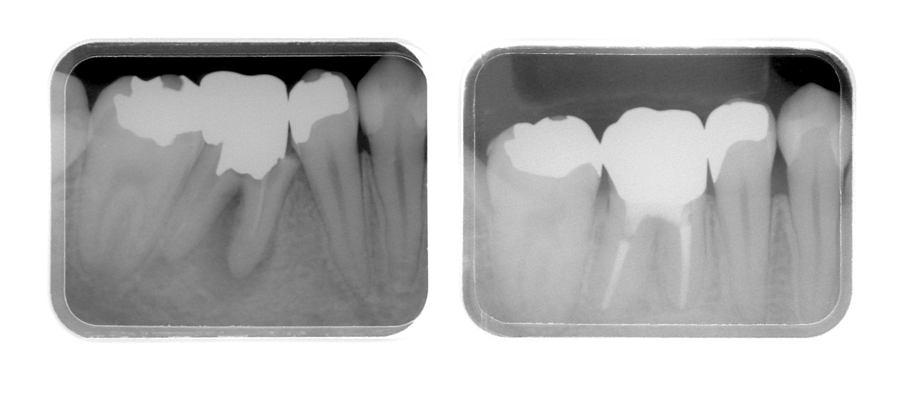

| 主訴 | 50代女性 他院でいれた入れ歯の具合が良くない。歯を白くしたい。歯並びも気になる。しっかり噛めるようになりたい |

| 治療内容 | インプラント治療、セラミック治療、金属床コーヌス義歯(部分入れ歯)を行いました。 |

| 治療費 | 2,400,000円(税込み) |

| 治療期間 | 8か月 |

| 治療回数 | 30回 |

| 想定されたリスク | 重度の歯周病で臼歯部の歯槽骨がかなり吸収していたため、インプラントが脱落するリスクがありました。 |